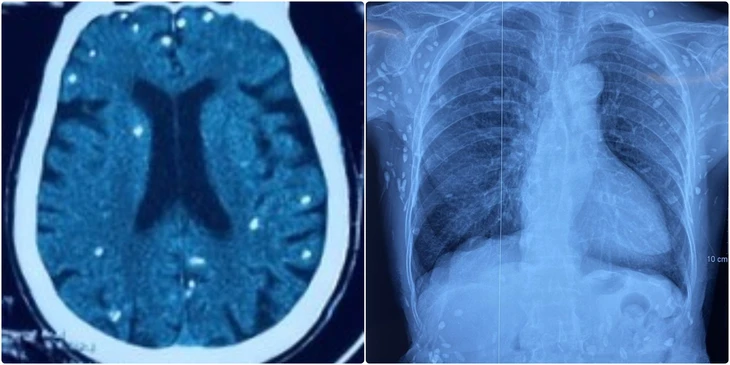

Hình ảnh chụp cắt lớp vi tính sọ não và X-quang ngực của bệnh nhân có nhiều tổn thương do nang sán - Ảnh: BVCC

Người bệnh được chuyển lên từ tuyến dước vì rối loạn ý thức, đe dọa suy hô hấp, hình ảnh cắt lớp vi tính sọ não và X-quang ngực cho thấy rất nhiều nốt cản quang trong nhu mô não và dưới da vùng ngực - bụng.

Khám lâm sàng phát hiện một số u cục với kích thước tương ứng có thể sờ thấy dưới da vùng ngực và cánh tay của người bệnh.

Theo bác sĩ Nguyễn Thị Vân Anh, khoa hồi sức truyền nhiễm, Bệnh viện Trung ương Quân đội 108, mặc dù xét nghiệm kháng thể IgM với sán dây lợn âm tính, các tổn thương trên X-quang gợi ý người bệnh trước đây bị nhiễm ấu trùng sán dây lợn, sau đó các nang sán trở nên vôi hóa và tồn tại lâu dài trong cơ thể.

"Nang sán dây lợn có thể tự thoái hóa hoặc bị vôi hóa, tạo nên nhiều hình ảnh cản quang phát hiện được trên phim X-quang như trường hợp bệnh nhân trên", bác sĩ Thấu cho hay.